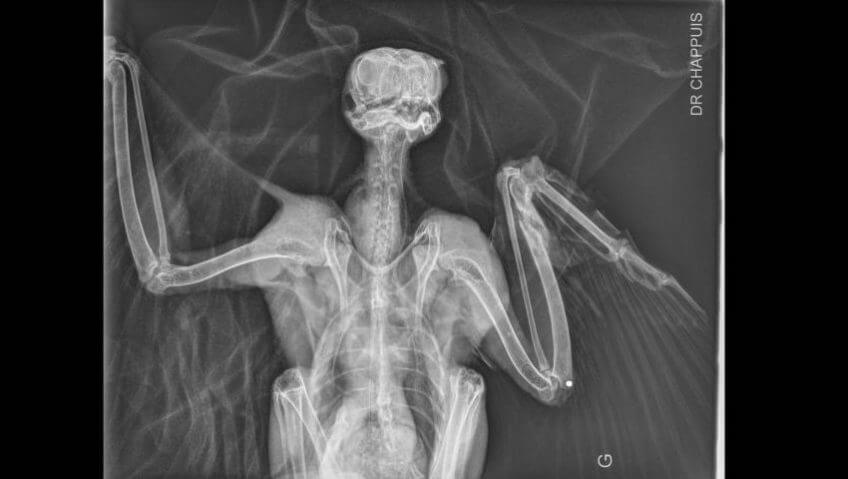

Radiographie du faucon / © Dr. Chappuis, Adrien Corsi / LPO Auvergne

L’impression 3D au secours des oiseaux - La Salamandre radiographie

Radiographie du faucon. / © Dr. Chappuis, Adrien Corsi / LPO Auvergne